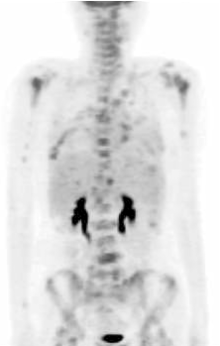

2009年5月患者自行发现右乳肿物, 遂于我院门诊行乳腺B超检查, 疑右乳腺癌保乳术后复发而收入院。入院后行PET检查示右乳腺癌保乳术后局部复发, 并全身多发性转移(见图1)。予化疗6周期后, 部分缓解。遂于2009年10月行右乳单纯切除术。术后病理结果示:(右侧) 乳腺浸润性导管癌, Ⅱ 级。肿瘤最大径无法准确评估; 未见明确脉管癌栓及神经束膜侵犯; 乳头及皮肤未见Paget’ s病; 各切缘及皮肤切缘均未见肿瘤。术后再予化疗2周期, 并予内分泌治疗, 嘱患者定期复查。